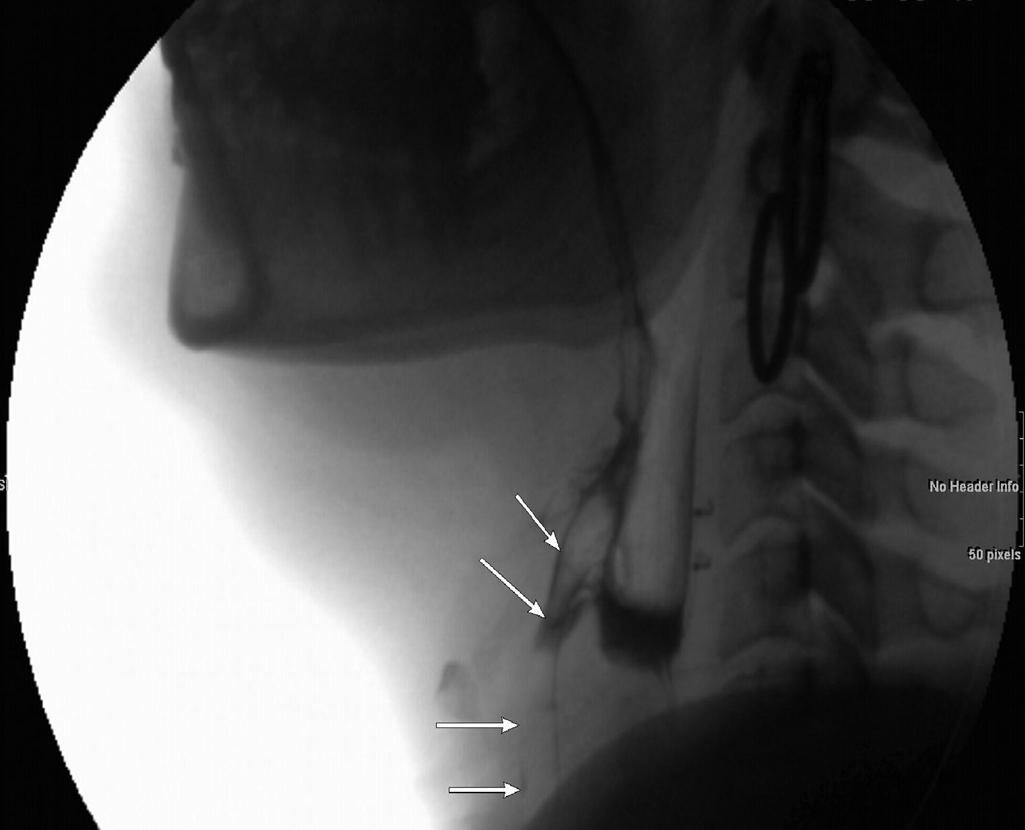

Various noninstrumental examinations (volume-viscosity swallow test, Eating Assessment Tool 10) as well as instrumental examinations (videofluoroscopic swallowing study [VFSS] or fiberoptic endoscopic evaluation of swallowing [FEES]) can be utilized to evaluate and screen patients with MND for dysphagia. VFSS, in conjunction with an oropharyngeal examination by a speech pathologist, can provide a more objective measurement of swallowing ( ). Videofluoroscopy involves the swallowing by the patient of barium suspension of varying consistency, fluid and semisolid. An analysis of the various stages of swallowing is made, and laryngeal penetration can be reliably detected by videofluoroscopy. Videofluoroscopy can also help guide decisions about feeding regimes and estimate the patient’s risk of respiratory complications from oral feeding. Videofluoroscopy could be used to assess risks of aspiration. The presence of laryngeal penetration on videofluoroscopy in the setting of clinical dysphagia indicates a high risk of aspiration pneumonia ( Figs. 4.1 and 4.2 ). Cineradiographic studies of the pharynx in MD patients have revealed abnormalities such as weak and asymmetric contractions of the pharynx and cricopharyngeus, myotonia of the tongue and pharynx with stasis, and pooling of contrast in the pyriform sinuses and valleculae. The combined techniques of videofibrolaryngoscopy and videofluoroscopy can be the best methods for evaluating dysphagia.

Fig. 4.2, Modified barium swallow with aspiration: on the lateral image, arrows show abnormal spillover with aspiration.